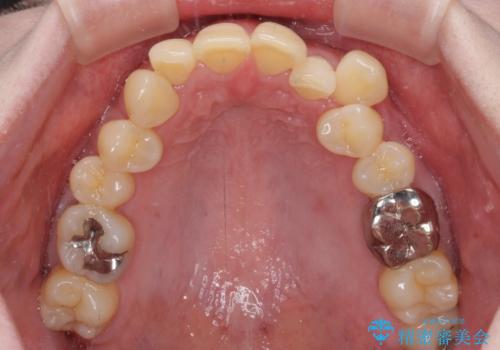

- 八重歯と正中のズレを気にして来院された患者様です。

上顎左側が八重歯になっており、上顎正中が左側にずれていました。

上顎左側の第一小臼歯を抜歯し、補助装置を用いて正中位置を改善しながら八重歯を解消していくこととしました。

下顎前歯が1本欠損していたため、上下正中の位置が合わせるという目標はなく、鼻筋に上顎正中を合わせていくように移動を行いました。